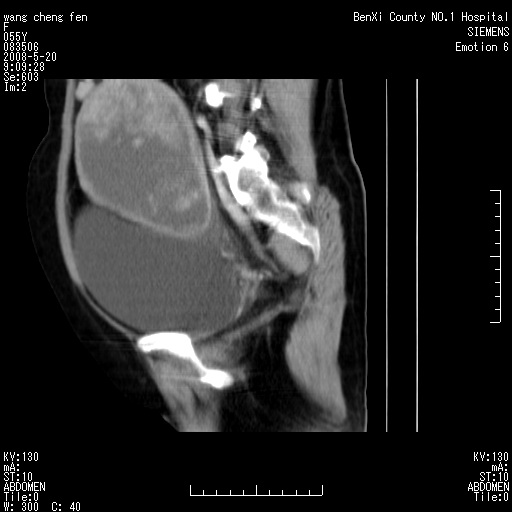

女、绝经后阴道流血3个月

左侧附件区巨大囊实性病灶,边缘光整,病灶囊壁较厚,增强示囊壁及实性部分明显强化,强化呈度与宫体实质大致相同,宫腔积液征像,未见盆腔积液等其他异常,考虑左侧卵巢囊腺癌,不除外囊腺瘤及浆膜下肌瘤坏死

左侧附件区巨大囊实性病灶,边缘光整,病灶囊壁较厚,增强示囊壁及实性部分明显强化,强化呈度与宫体实质大致相同,宫腔积液征像,未见盆腔积液等其他异常。绝经后阴道流血3个月,结合病史左侧卵巢囊腺癌首先考虑,宫腔扩大不除外累及。期待结果。

囊实性肿块分隔厚度较大,厚薄不均,增强实性成分明显强化,有不规则阴道流血,卵巢囊腺癌可能性大。

1,宫颈部占位,宫颈癌?2,左侧附件区囊实性占位,界较清,实质部分强化明显。考虑浆膜下或阔韧带肌瘤囊变可能大。囊腺类肿瘤不除外。